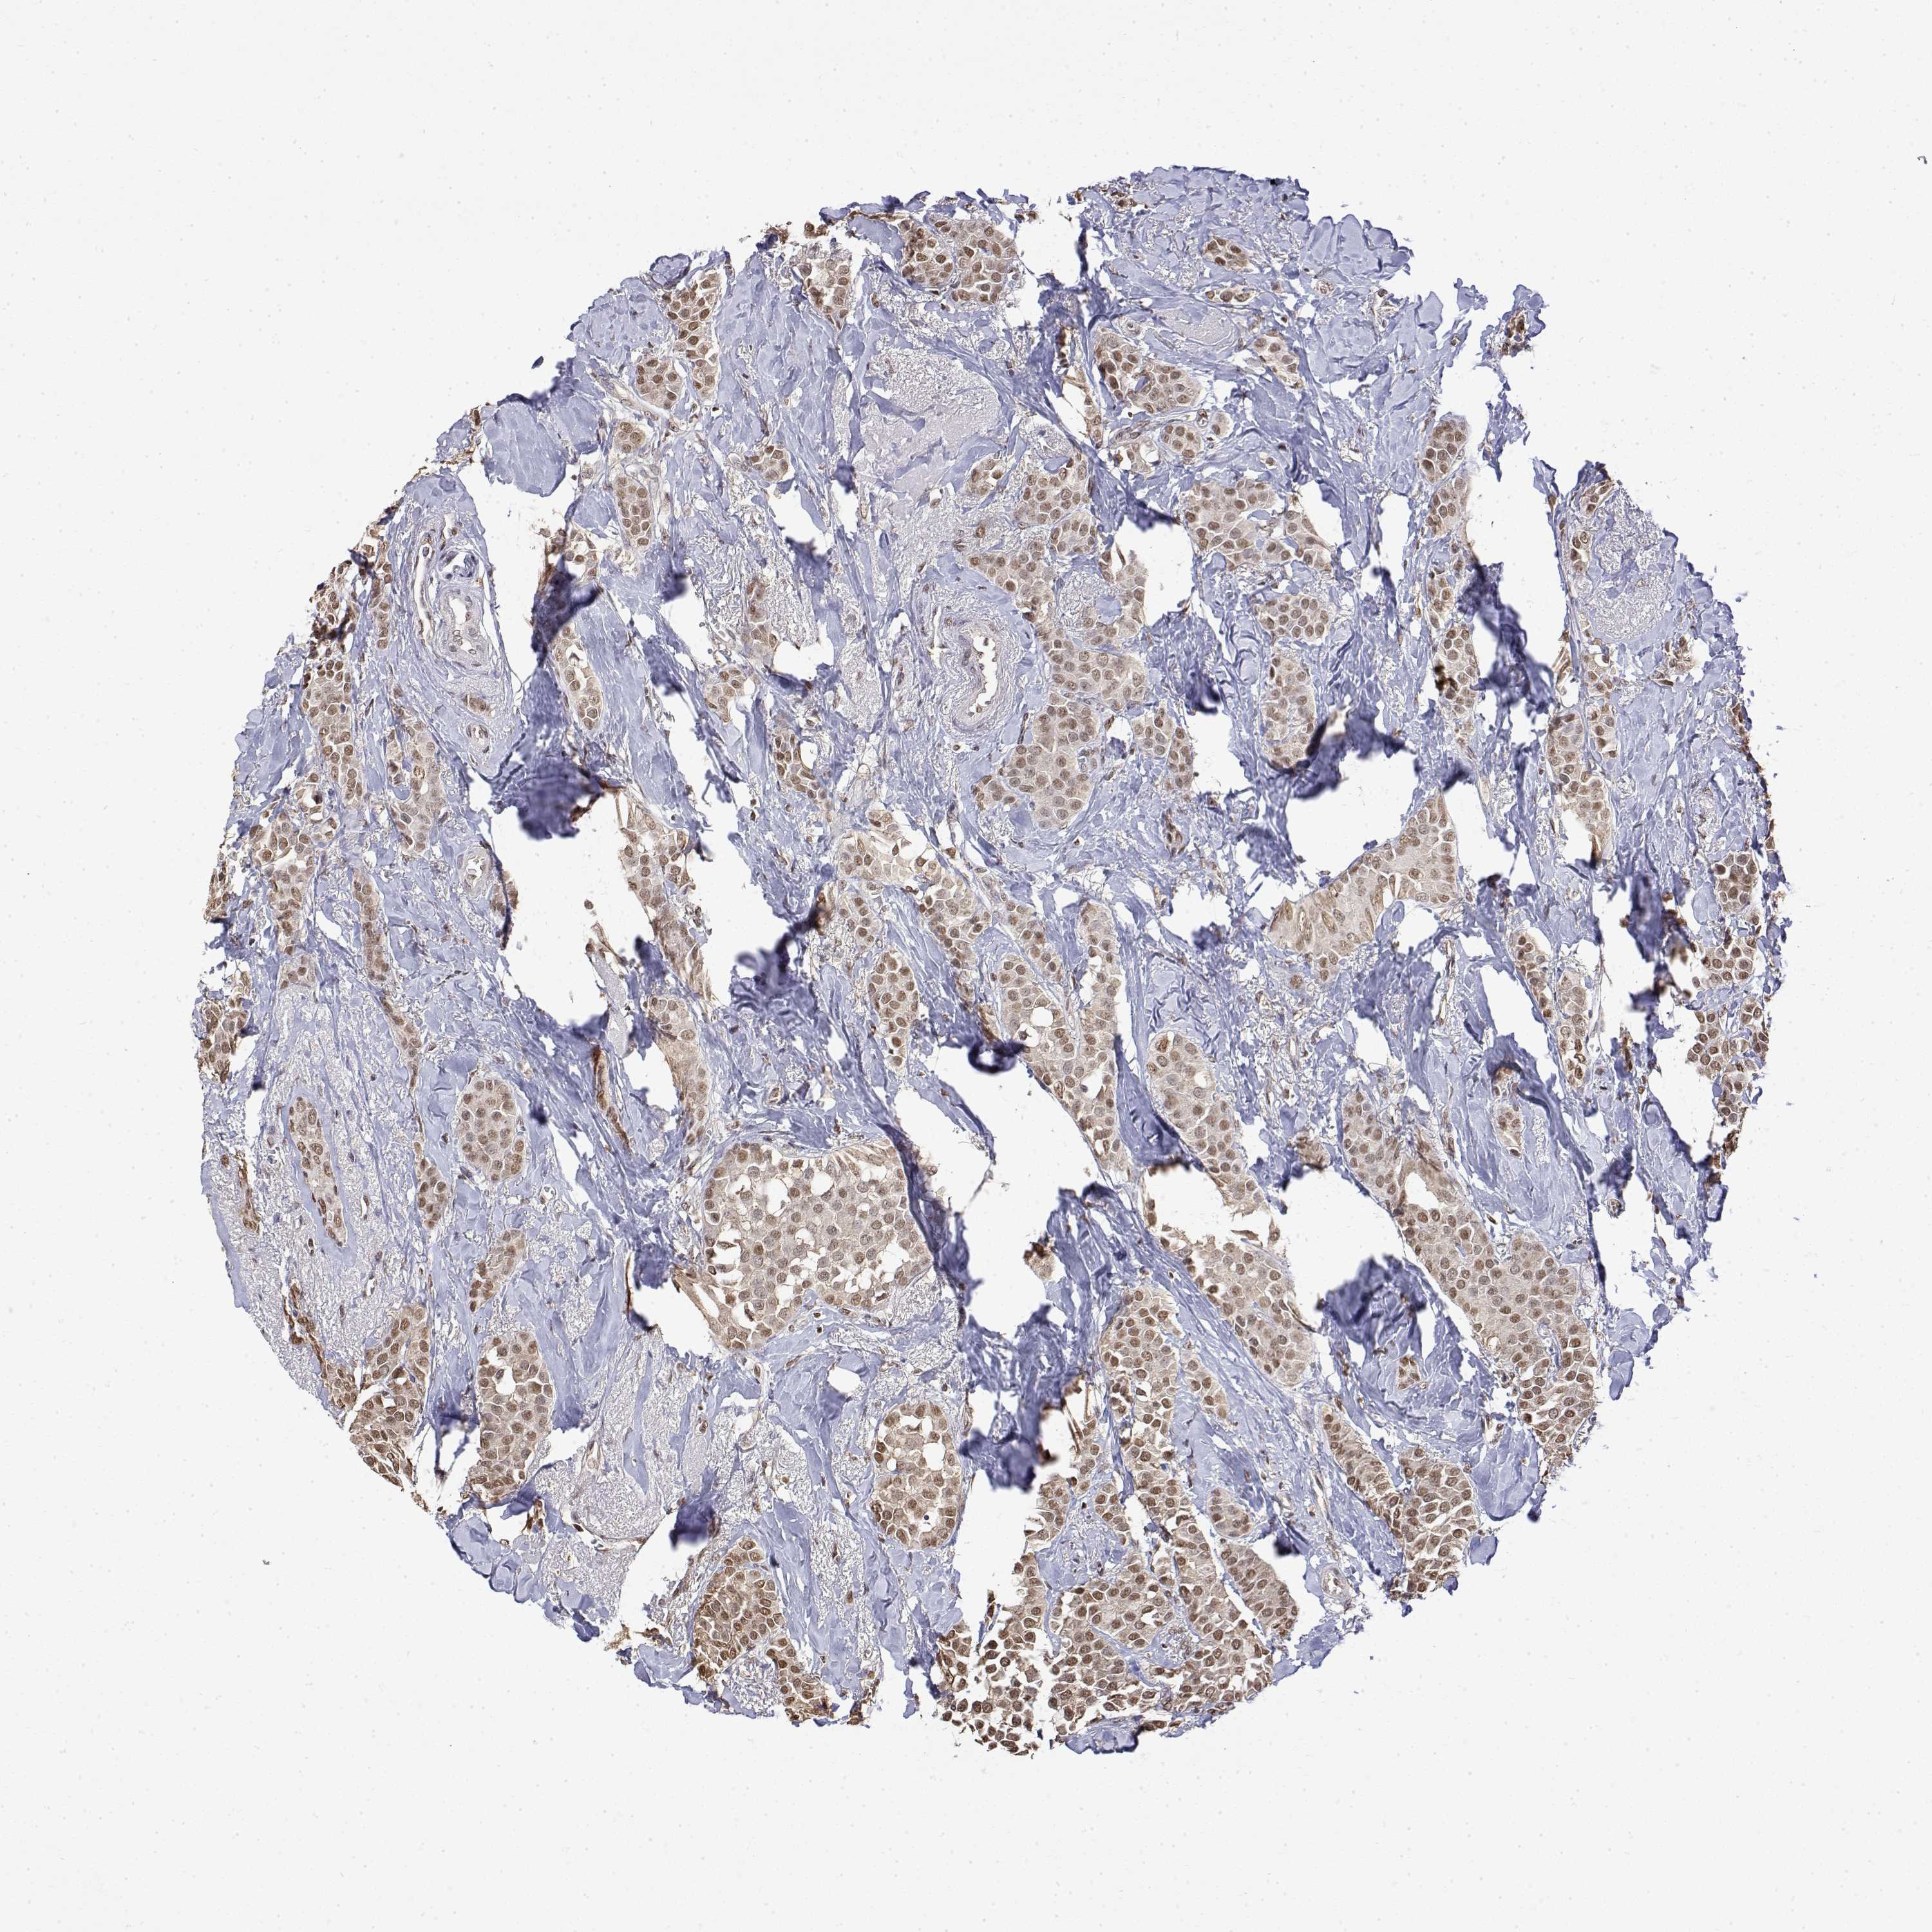

BRCA TCGA BRCA VALIDATION PROTEIN EXPRESSION